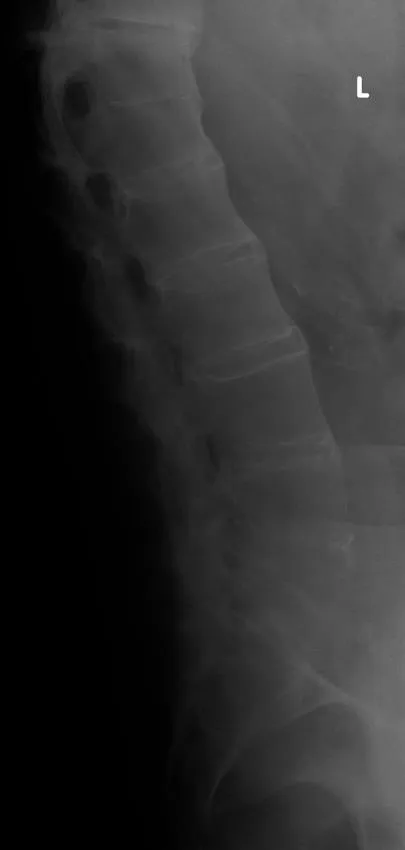

Age: 72 years | Gender: Male |

Clinical problem: Back pain following a fall | |

Images in exam case: Plain radiograph (4), CT (2) | |

- 2. CT whole spine:

- a. Ossification of anterior longitudinal ligament

- b. Fusion of multiple facet joints

- c. Severe cervicothoracic kyphosis

- d. Fracture line starting at D5/6 intervertebral disc and extending into the posterosuperior body of D6 and D6/7 facet joints

- e. Mild retrolisthesis of D5 over D6

DIAGNOSIS

- 1. Ankylosing spondylitis, acute fracture through D5/6 extending through the posterior elements. This is an unstable fracture as all three vertebral columns are disrupted.

Ankylosing spondylitis is a regular feature of the FRCR 2B examination, either as a written case or in the viva. The scenarios involved could be bilateral symmetrical sacroiliac joint erosion, sclerosis or fusion, erosion of the anterosuperior corner of the vertebra on lateral radiograph (Romanus sign), sclerosis of the anterosuperior corner and periostitis of the waist giving rise to vertebral ‘squaring’, syndesmophyte formation leading to ‘bamboo spine’, intervertebral disc calcification, ossification of the anterior longitudinal, posterior longitudinal, interspinous and supraspinous ligaments, kyphosis and facet joint fusion. Other skeletal features include erosions of the symphysis pubis and ischial tuberosities, asymmetrical erosive oligoarthritis, atlanto-axial dislocation and osteoporosis. In a traumatic setting, the fracture line may run through the intervertebral disc space right through into the posterior elements, and may be missed if one is not vigilant. Clinically occult fractures can also occur, leading to mobile non-union (pseudoarthrosis) – the so-called Anderson lesion.